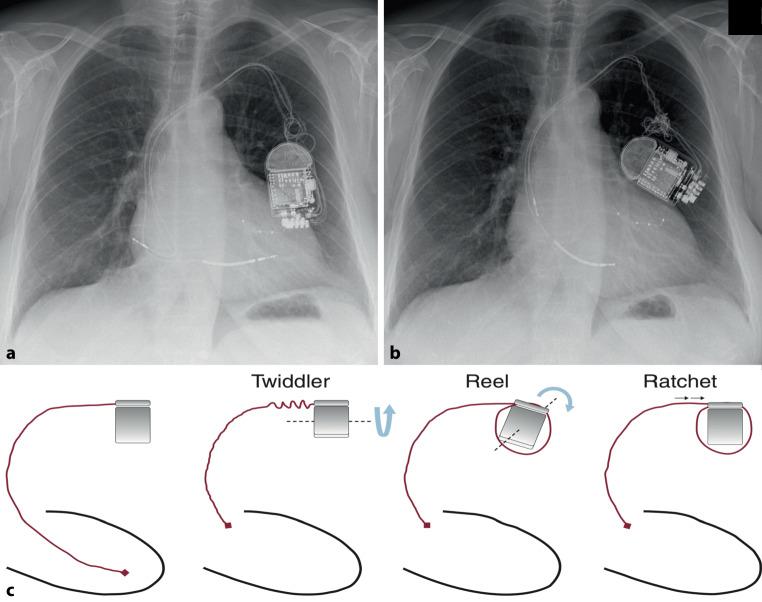

Twists and turns: CRT-D with mixed Twiddler and Reel syndromes.